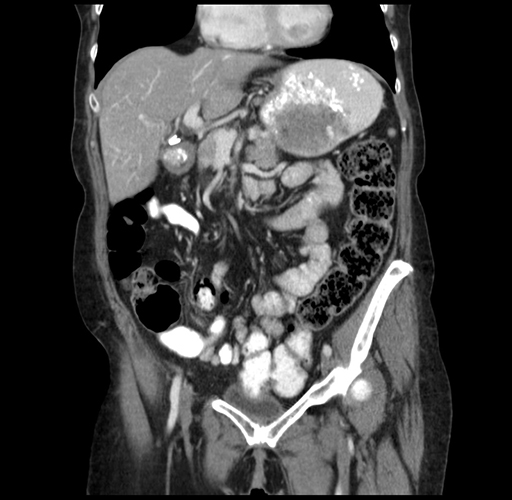

Axial Venous

Coronal Venous

Imaging analysis

Based on your CT findings, which issue(s) would give reason for "planned slowing down moment(s)" in this case?

Considering a standard right hepatectomy procedure, what step(s) of the operation would you do differently in this case?